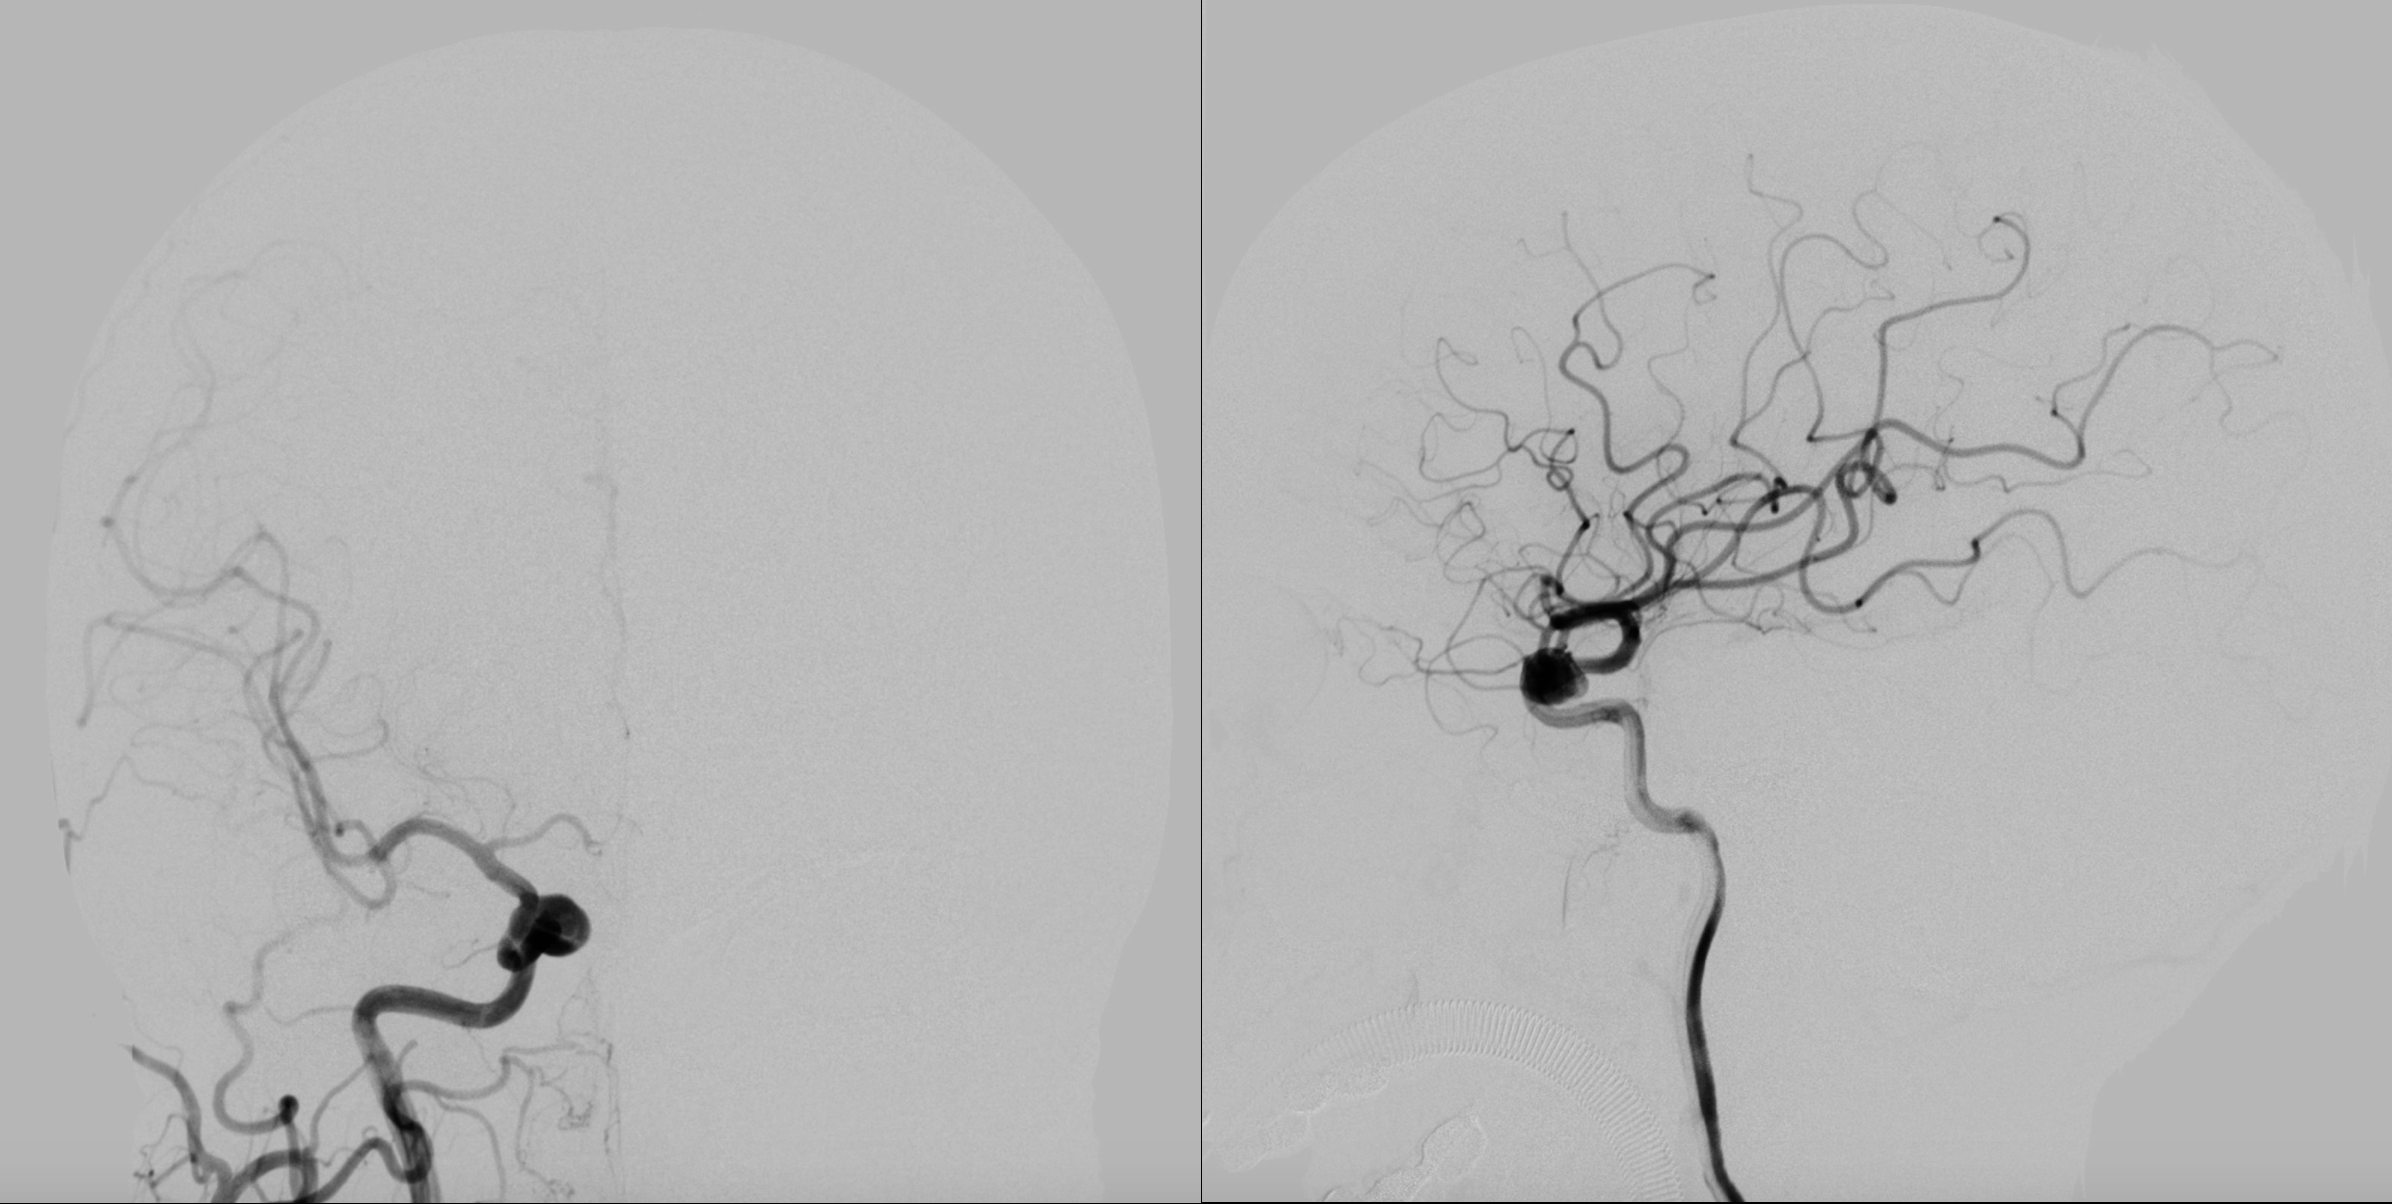

右侧颈内动脉正侧位造影:眼动脉段动脉瘤。

右侧颈内动脉三位造影重建:眼动脉段动脉瘤。给予支架辅助栓塞治疗。